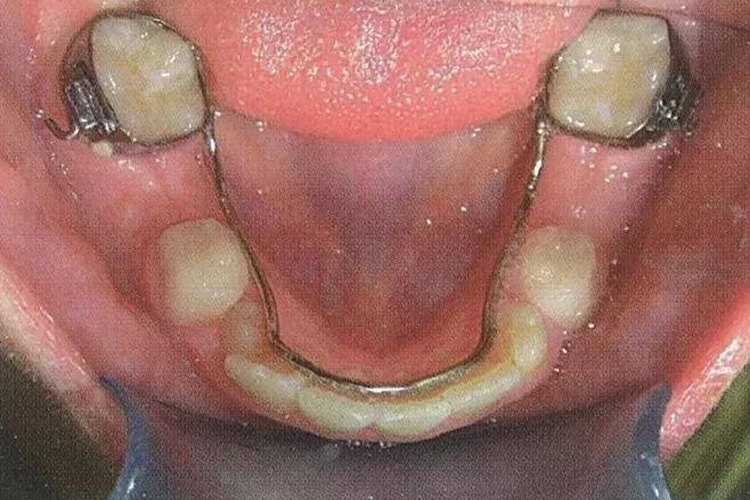

舌弓式间隙保持器

适用于下颌多颗后牙缺失的儿童,在双侧第一恒磨牙或第二乳磨牙上粘接带环,并在舌侧焊接舌弓,舌弓前部贴在下颌切牙的舌侧,保持牙弓长度。使用这种保持器,主要需要控制时间,以免影响牙弓发育。